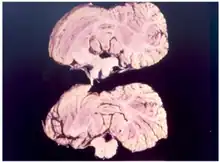

Diagnosis

Kuru is diagnosed by reviewing the patient's history of cerebellar signs and symptoms, performing neurological exams, and excluding other neurological diseases during exams.[15] The symptoms evaluated are typically coordination issues and involuntary muscle movements, but these markers can be confused with other diseases that affect the nervous and muscle system; physical scans are often required to differentiate Kuru from other disorders.[26][27] There is no laboratory test to determine the presence of Kuru, except for postmortem evaluation of central nervous system (CNS) tissues, so diagnoses are achieved by eliminating other possible disorders.

Electroencephalogram (EEG) is used to distinguish kuru from Creutzfeldt–Jakob disease, a similar encephalopathy (any disease that affects the structure of the brain).[27] EEGs search for electrical activity in the patient's brain and measure the frequency of each wave to determine if there is an issue with the brain's activity.[28] Periodic complexes (PC), reoccurring patterns with spike wave-complexes occurring at intervals, are recorded frequently in some diseases but are not presented in the kuru readings.[29] Exams and testing, like EEG, MRIs, blood test, and scans, can be used to determine if the infected person is dealing with Kuru disease or another encephalopathy. However, testing over periods of time can be difficult.